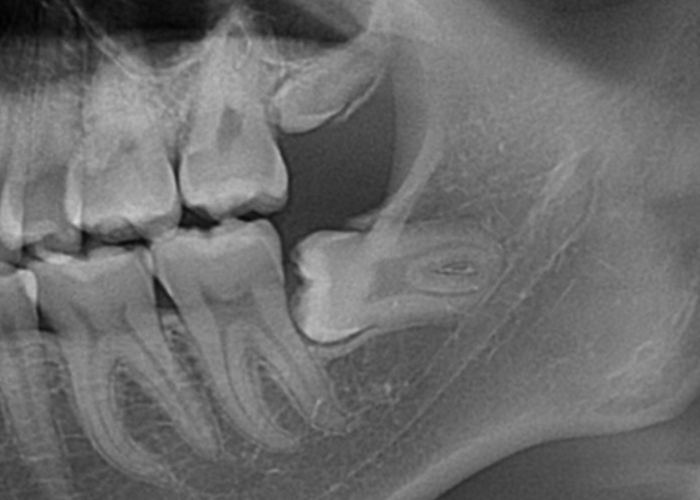

パノラマX線写真を撮影し親知らずの位置関係を把握します。

深さによってはCTまで撮影し3次元的な位置関係の把握を行います。その後局所麻酔と口腔内の清掃を行った上で抜歯します。

親知らずの頭や周囲の骨が引っかかって抜きづらい場合は親知らずを分割したり、周囲の骨を部分的に削除しながら親知らずの抜歯を行います。